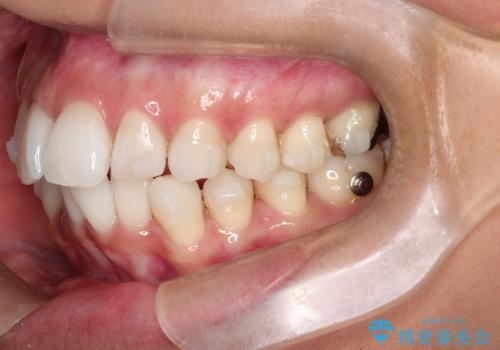

- 前歯の重なり(叢生)をきれいに整えたいという主訴でご来院されました。

精密検査の結果、歯を並べるためのスペースが不足していましたが、抜歯をせずに改善したいというご希望があったため、IPR(歯の側面をわずかに削る処置)と、奥歯を後ろに動かす「遠心移動」を組み合わせる計画を立案。透明なマウスピース装置であるインビザラインを使用し、無理のない範囲でスペースを確保しながら歯列を整えることとしました。

治療では、マウスピースの設計に基づき、奥歯から順に後ろへ移動させる遠心移動を行い、前歯のためのスペースを作りました。同時に、数箇所の歯の間にIPRを施すことで、歯の健康に影響のない範囲で精密に隙間を確保しました。

1年半の治療期間を経て、重なり合っていた前歯はスムーズに整列し、理想的なアーチ状の歯並びへと改善されました。抜歯を行わずに治療を完了したことで、噛み合わせのバランスを維持しながら、審美性を大きく向上させることができました。現在は保定期間に入り、美しい状態を維持されています。